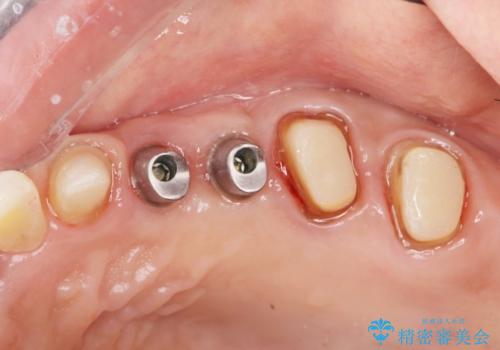

- 154万円(インプラント×2・チタンカスタムアバットメント×2・ジルコニアクラウン×6・仮歯×6)費用は治療当時の料金となります

銀歯の下で虫歯が再発していた歯は、無理に残しても割れてしまう可能性が非常に高いと考えたため、相談の上抜去を行いインプラント治療を行っていくこととしました。